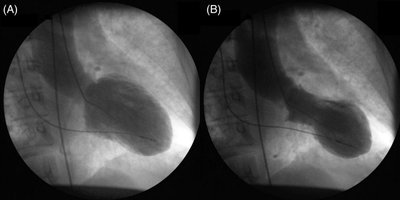

Takotsubo cardiomyopathy is an acute, reversible cardiac syndrome often triggered by emotional or physical stress. It is more prevalent in women and is characterized by transient left ventricular dysfunction, typically involving the apex (apical ballooning).

Imaging: Apical akinesis with preserved basal contraction

Pathophysiology | Ventricular dilation, reduced contractility | Transient apical ballooning, catecholamine surge |

Imaging | Dilated chambers, thin walls | Apical akinesis, ballooning |